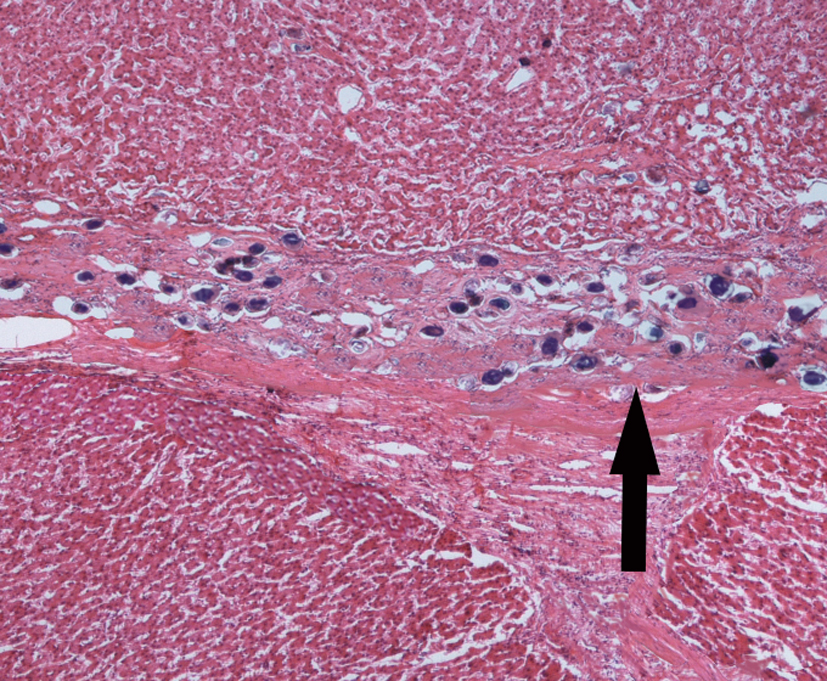

4.Pile-stem liver fibrosis of schistosomiasis